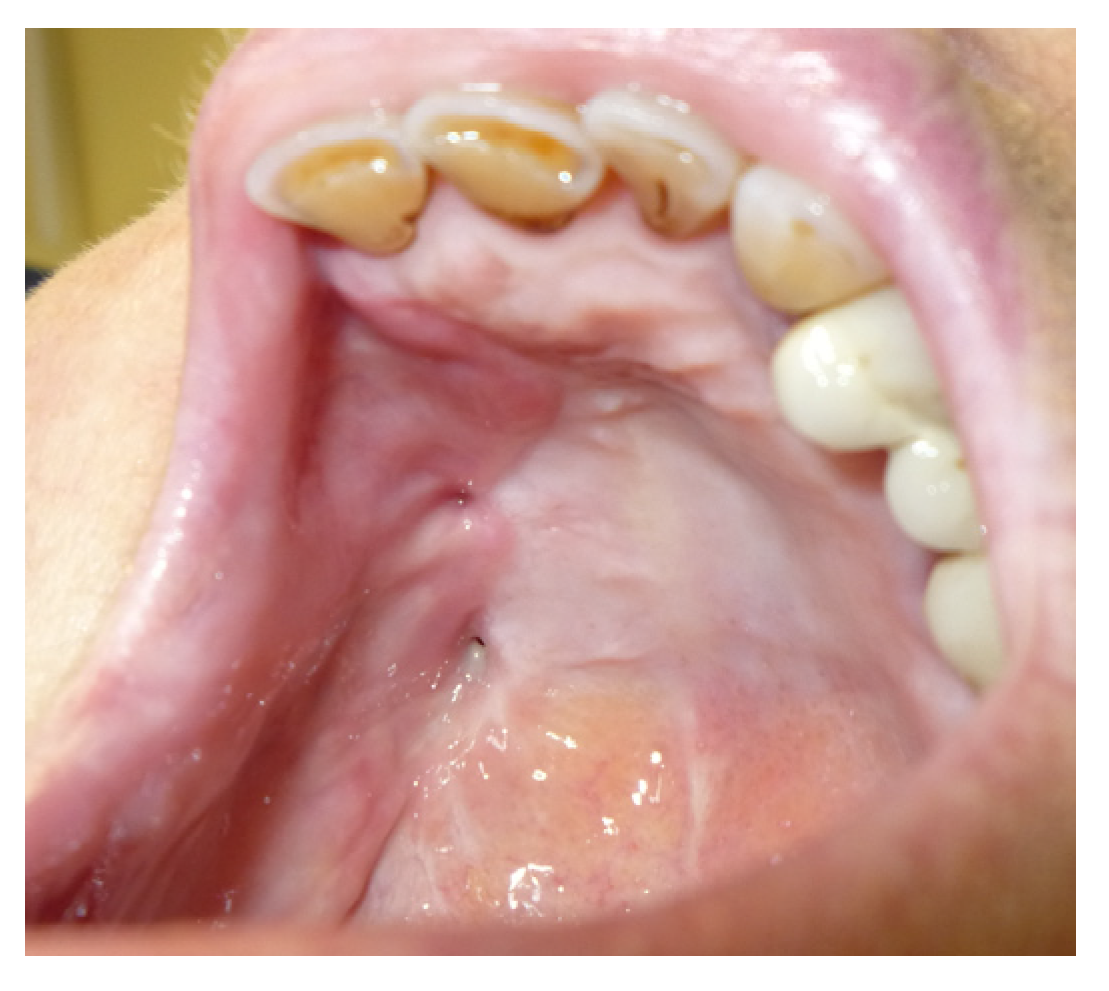

3.1.1. Case 1: A.R.

| A.R | X | * | 5 | 1 | ||